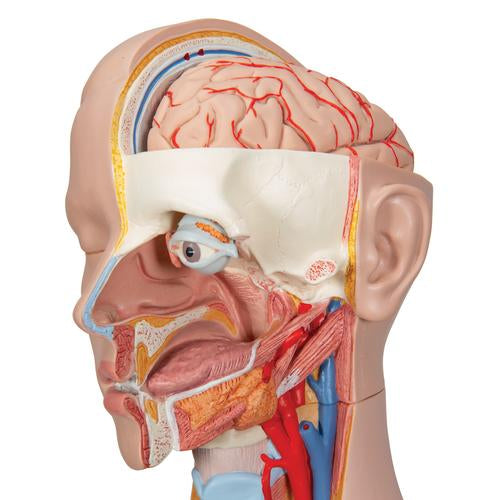

This meticulously crafted torso is expertly hand-painted with precision and made from high-quality plastic. All 3B torsos are designed and produced in Germany. This unisex human torso model features a distinctive open neck and back section extending from the cerebellum to the coccyx. It accurately depicts vertebrae, intervertebral discs, spinal cord, spinal nerves, vertebral arteries, and numerous other components in this vibrant representation of human anatomy. This human torso model includes the following detachable parts and organs:

- 6-part head